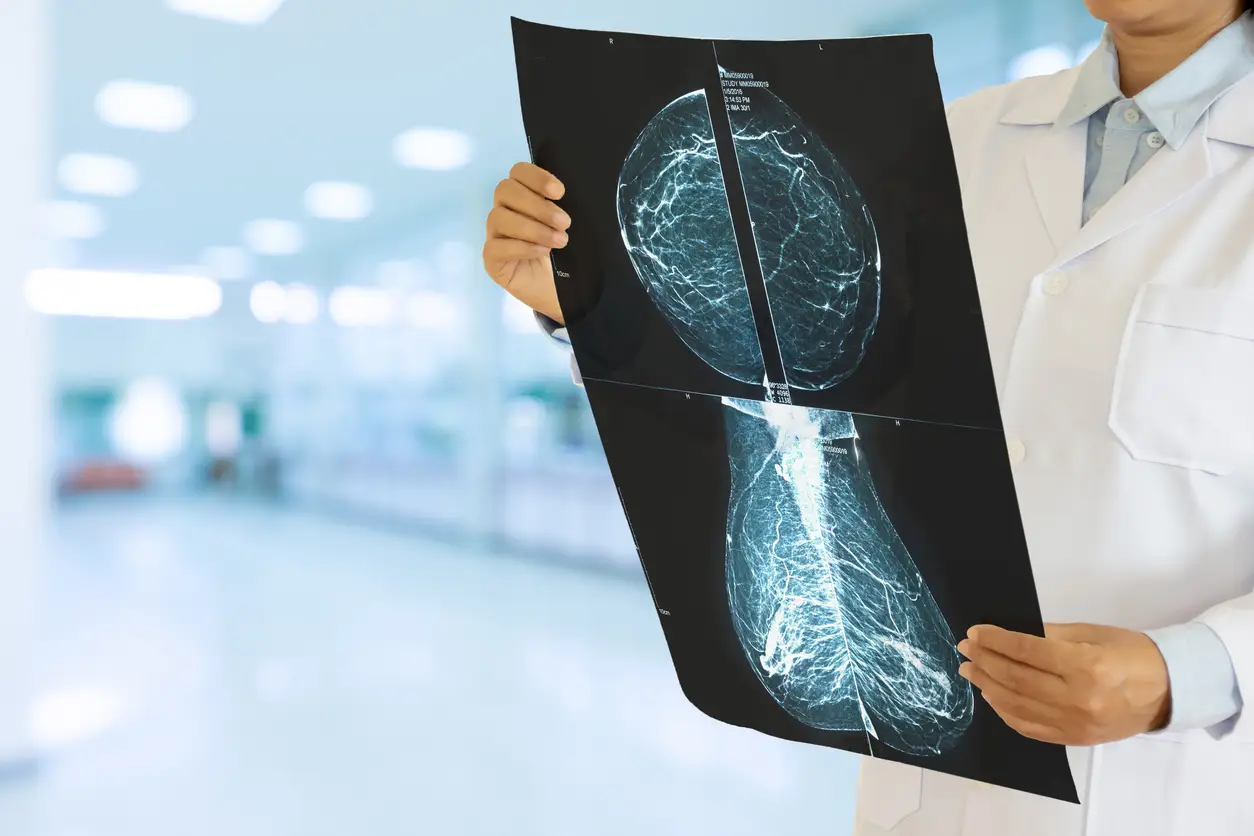

Conventional cancer screening usually looks at one part of the body — mammograms for breast cancer, or colonoscopies for colon cancer, for example. Whole-body MRI doesn’t wait around. It’s not as one-organ focused as it is whole organism-focused. This can be especially useful in those with a significant family history of cancer, or known gene mutations such as BRCA or Lynch syndromes. Sometimes, these scans will detect early, ominous signals of cancer in surprising locations — the lungs a long time before a cough, the liver before there is any hint of trouble there — in a way we wouldn’t screen for years later in a conventional lifetime.

Yet as cool as the concept of a full-body MRI may sound, there are also some pretty significant downsides to it. One is the false positive rate, when scans reveal benign spots that can lead to more testing, anxiety or unnecessary procedures, which is why it is even more critical to use a doctor who is good at interpreting the results and telling you what is actionable and what is not. Not even full-body scanners can make the old tests (colonoscopies, mammograms) entirely obsolete yet — but can nicely complement them.

Whole-body MRI is leading the way for a new kind of preventive care, providing people a way to do for themselves what can be done for a race car: screen for cancer and other diseases before they cause symptoms. There’s no radiation involved; it offers a more complete imaging solution. As such, it’s the best tool we have for catching the earliest signs of breast cancer. It is not a substitute for all old-fashioned tests, but it is a powerful supplement — and for many, a game changer. If you’re interested in taking control over your own long-term health, this could be the scan that puts you one step ahead.